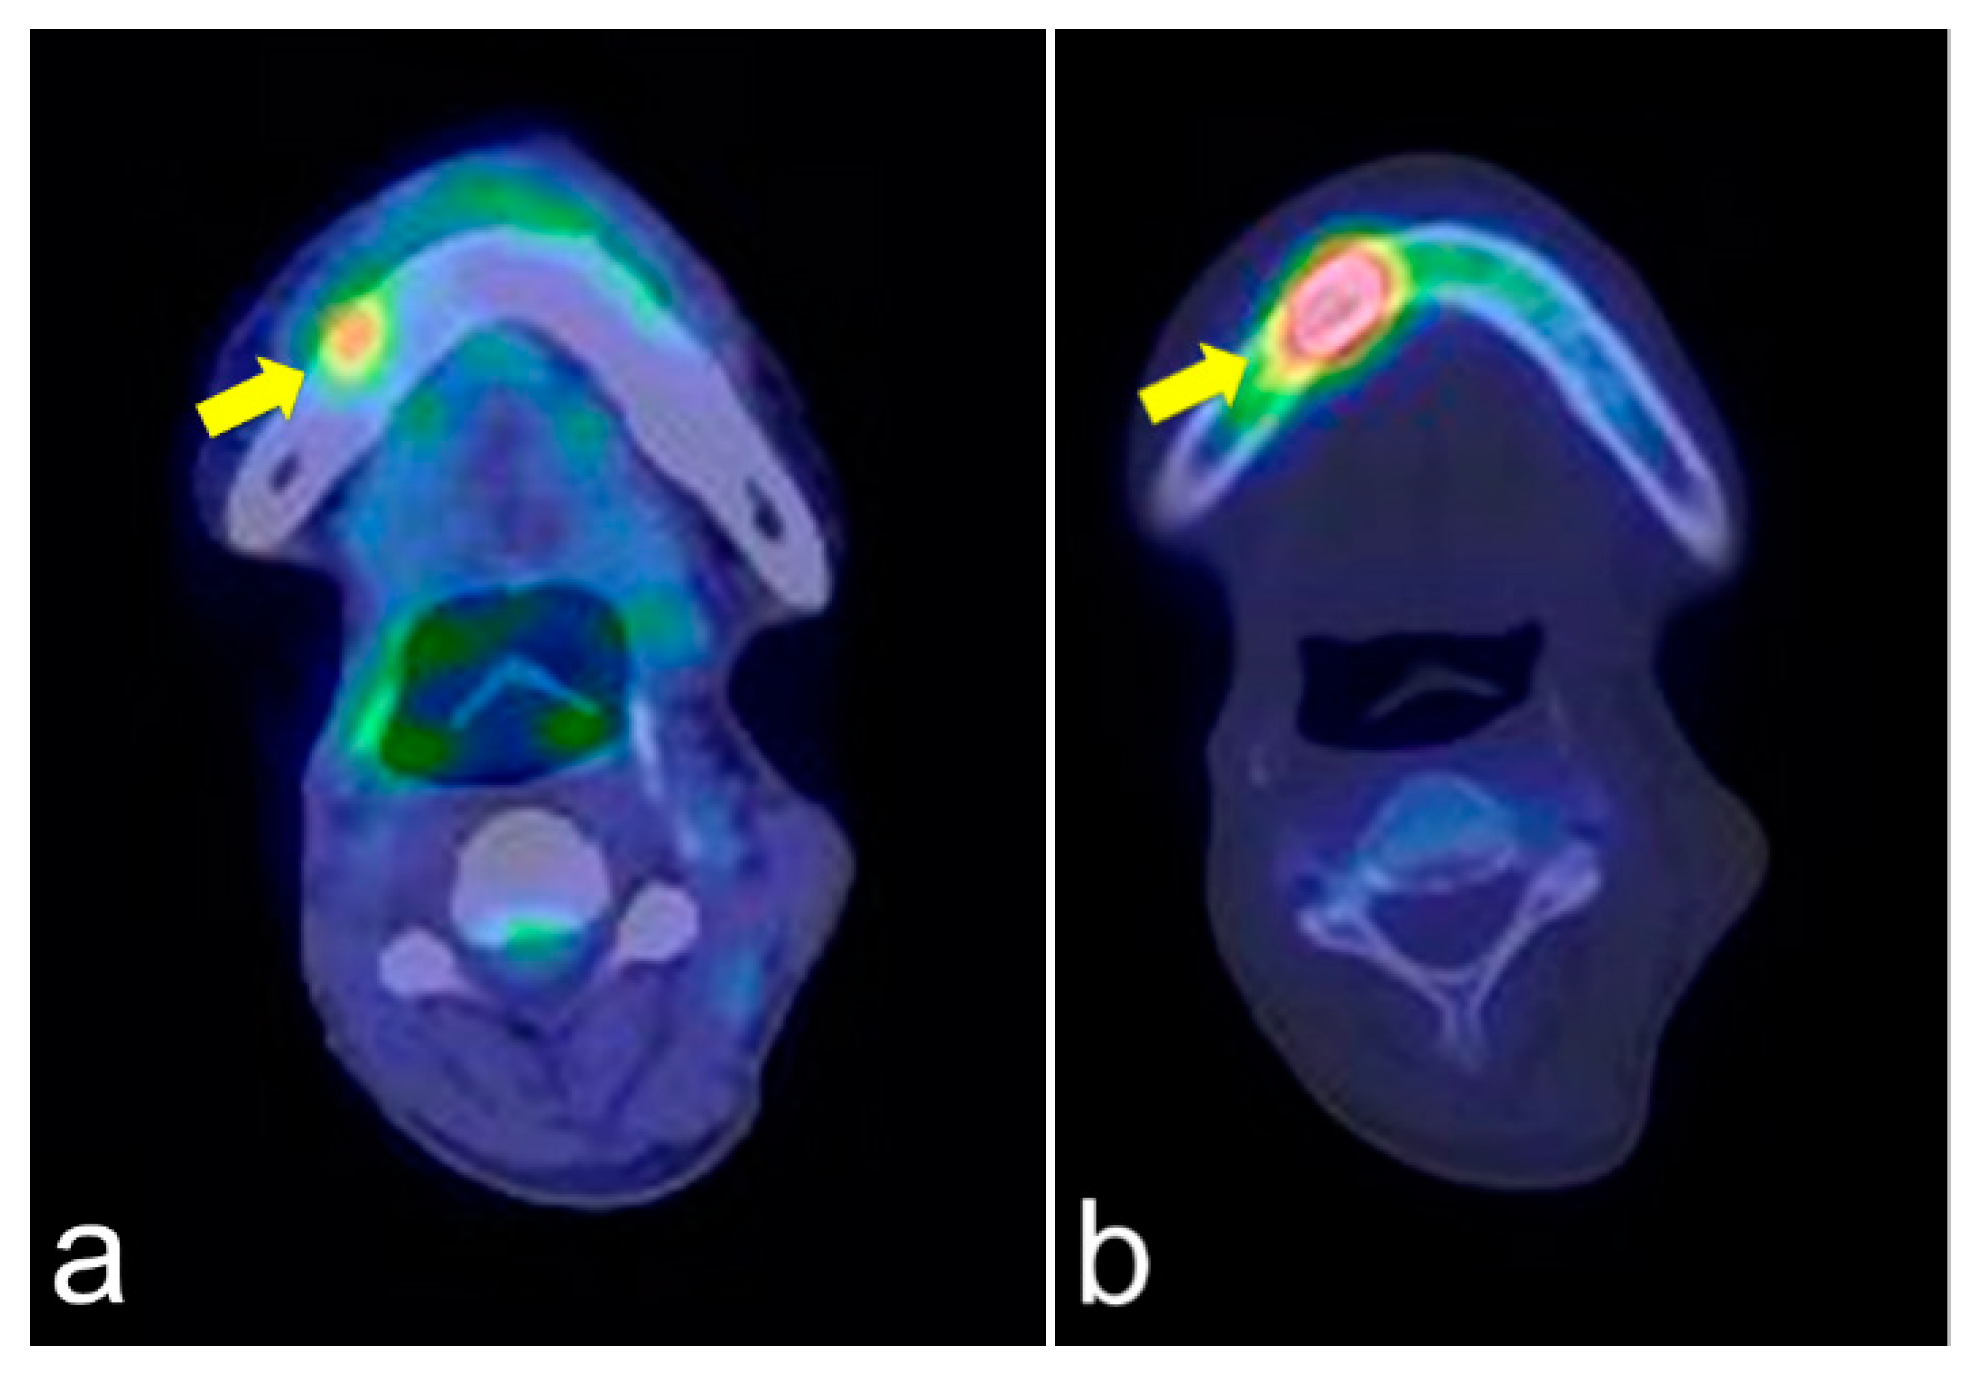

The same lesions captured by PET/CT and SPECT are shown in Figure 4a,b, respectively. PET/CT is useful for differentiating tumor recurrence. On the other hand, SPECT provides useful information regarding bone activity. PET/CT appeared to represent glucose metabolism, including the bone marrow, which was hyper-metabolized, and SPECT appeared to represent areas of increased bone metabolism; PET reflected inflammatory soft tissue and/or tumor recurrence and SPECT showed inflammatory and/or neoplastic bone tissue. PET/CT and SPECT are sensitive indicators of altered osteoblastic activity, but local disturbances in vascular perfusion, clearance rate, permeability, and chemical binding also affect imaging [13]. It is occasionally difficult to differentiate soft tissue uptake from bone uptake in patients with known cellulitis and possible underlying osteomyelitis. In terms of tumor recurrence, PET/CT and SPECT is useful but not definitive. Incisional biopsy is required for the final diagnosis.

Figure 4.

PET/CT (a) and single-photon emission computed tomography (SPECT) (b) images of the same lesion. PET/CT clearly shows soft tissue inflammation around the ORN area, while SPECT specifically shows bone inflammation. This comparison would help detect tumor recurrence.